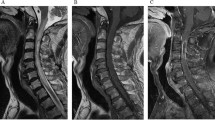

We report a 25-year-old gentleman who developed anterior spinal cord syndrome following the benzathine benzylpenicillin injection. In this case report, we discuss the clinical details, possible hypothesis behind spinal cord ischaemia and literature review.

Spinal cord ischaemia or infarction occurs due to embolism of the Penicillin products. The products following injection are carried as emboli retrogradely through the superior gluteal artery and can cause infarction to the cord’s anterior part.